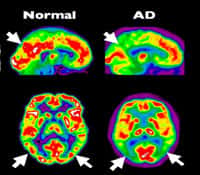

La maladie d'Alzheimermaladie d'Alzheimer est une maladie neurodégénérativemaladie neurodégénérative qui survient autour de 65 ans. Elle touche les fonctions cognitives et se répercute sur le comportement social des patients. À travers une approche interdisciplinaire, différents spécialistes font le point sur l'état actuel des recherches susceptibles d'apporter une meilleure compréhension des difficultés cognitives liées à l'âge et à Alzheimer.

Après avoir explicité les concepts de ressource adaptative et de mémoire chez l'adulte vieillissant, les auteurs livrent une analyse approfondie des mécanismes du vieillissement cérébral et de la maladie d'Alzheimer. Sont aussi passés en revue les différents facteurs de risquefacteurs de risque, les possibilités de préventionprévention, et les ouvertures thérapeutiques. Le but étant de faire apparaître la compatibilitécompatibilité et la complémentarité des approches psycho-sociales et biologiques.